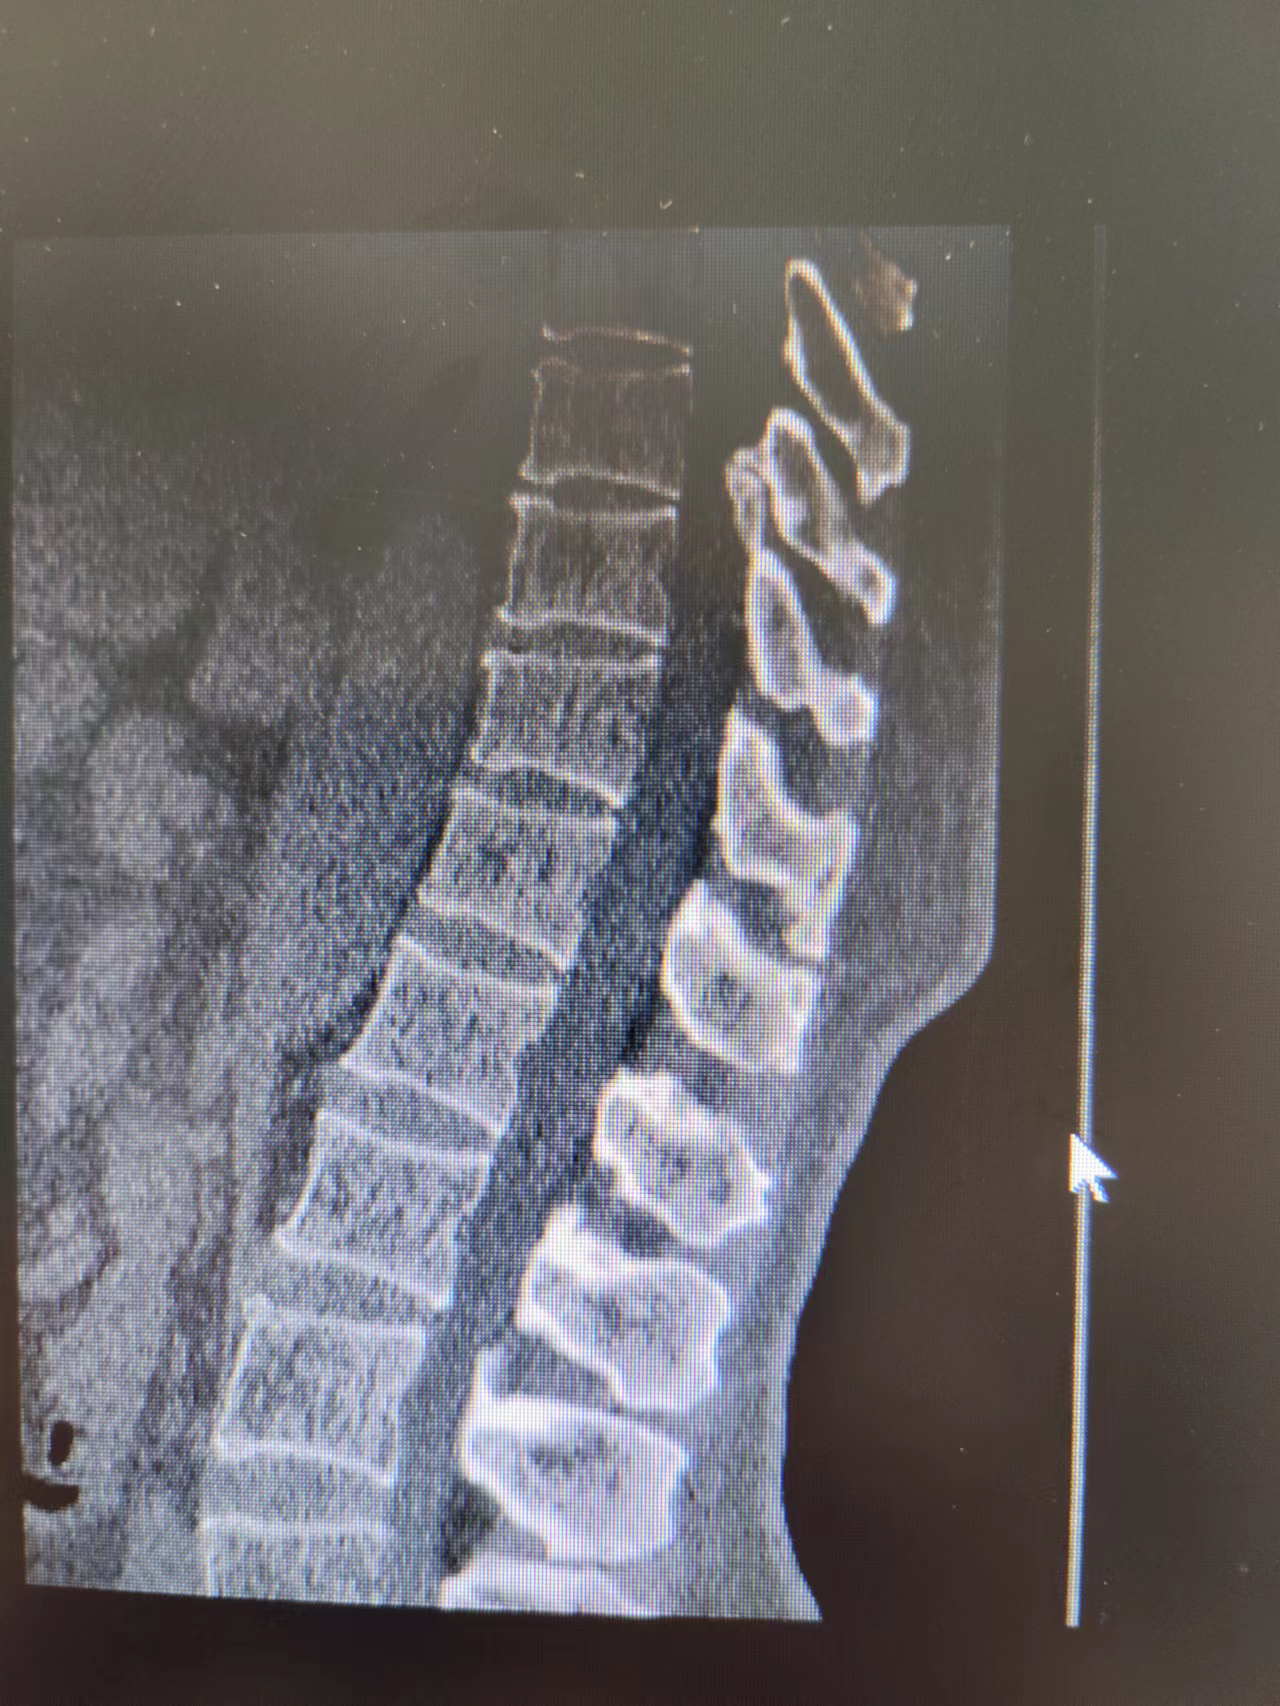

患者术前影像资料

患者术后影像资料